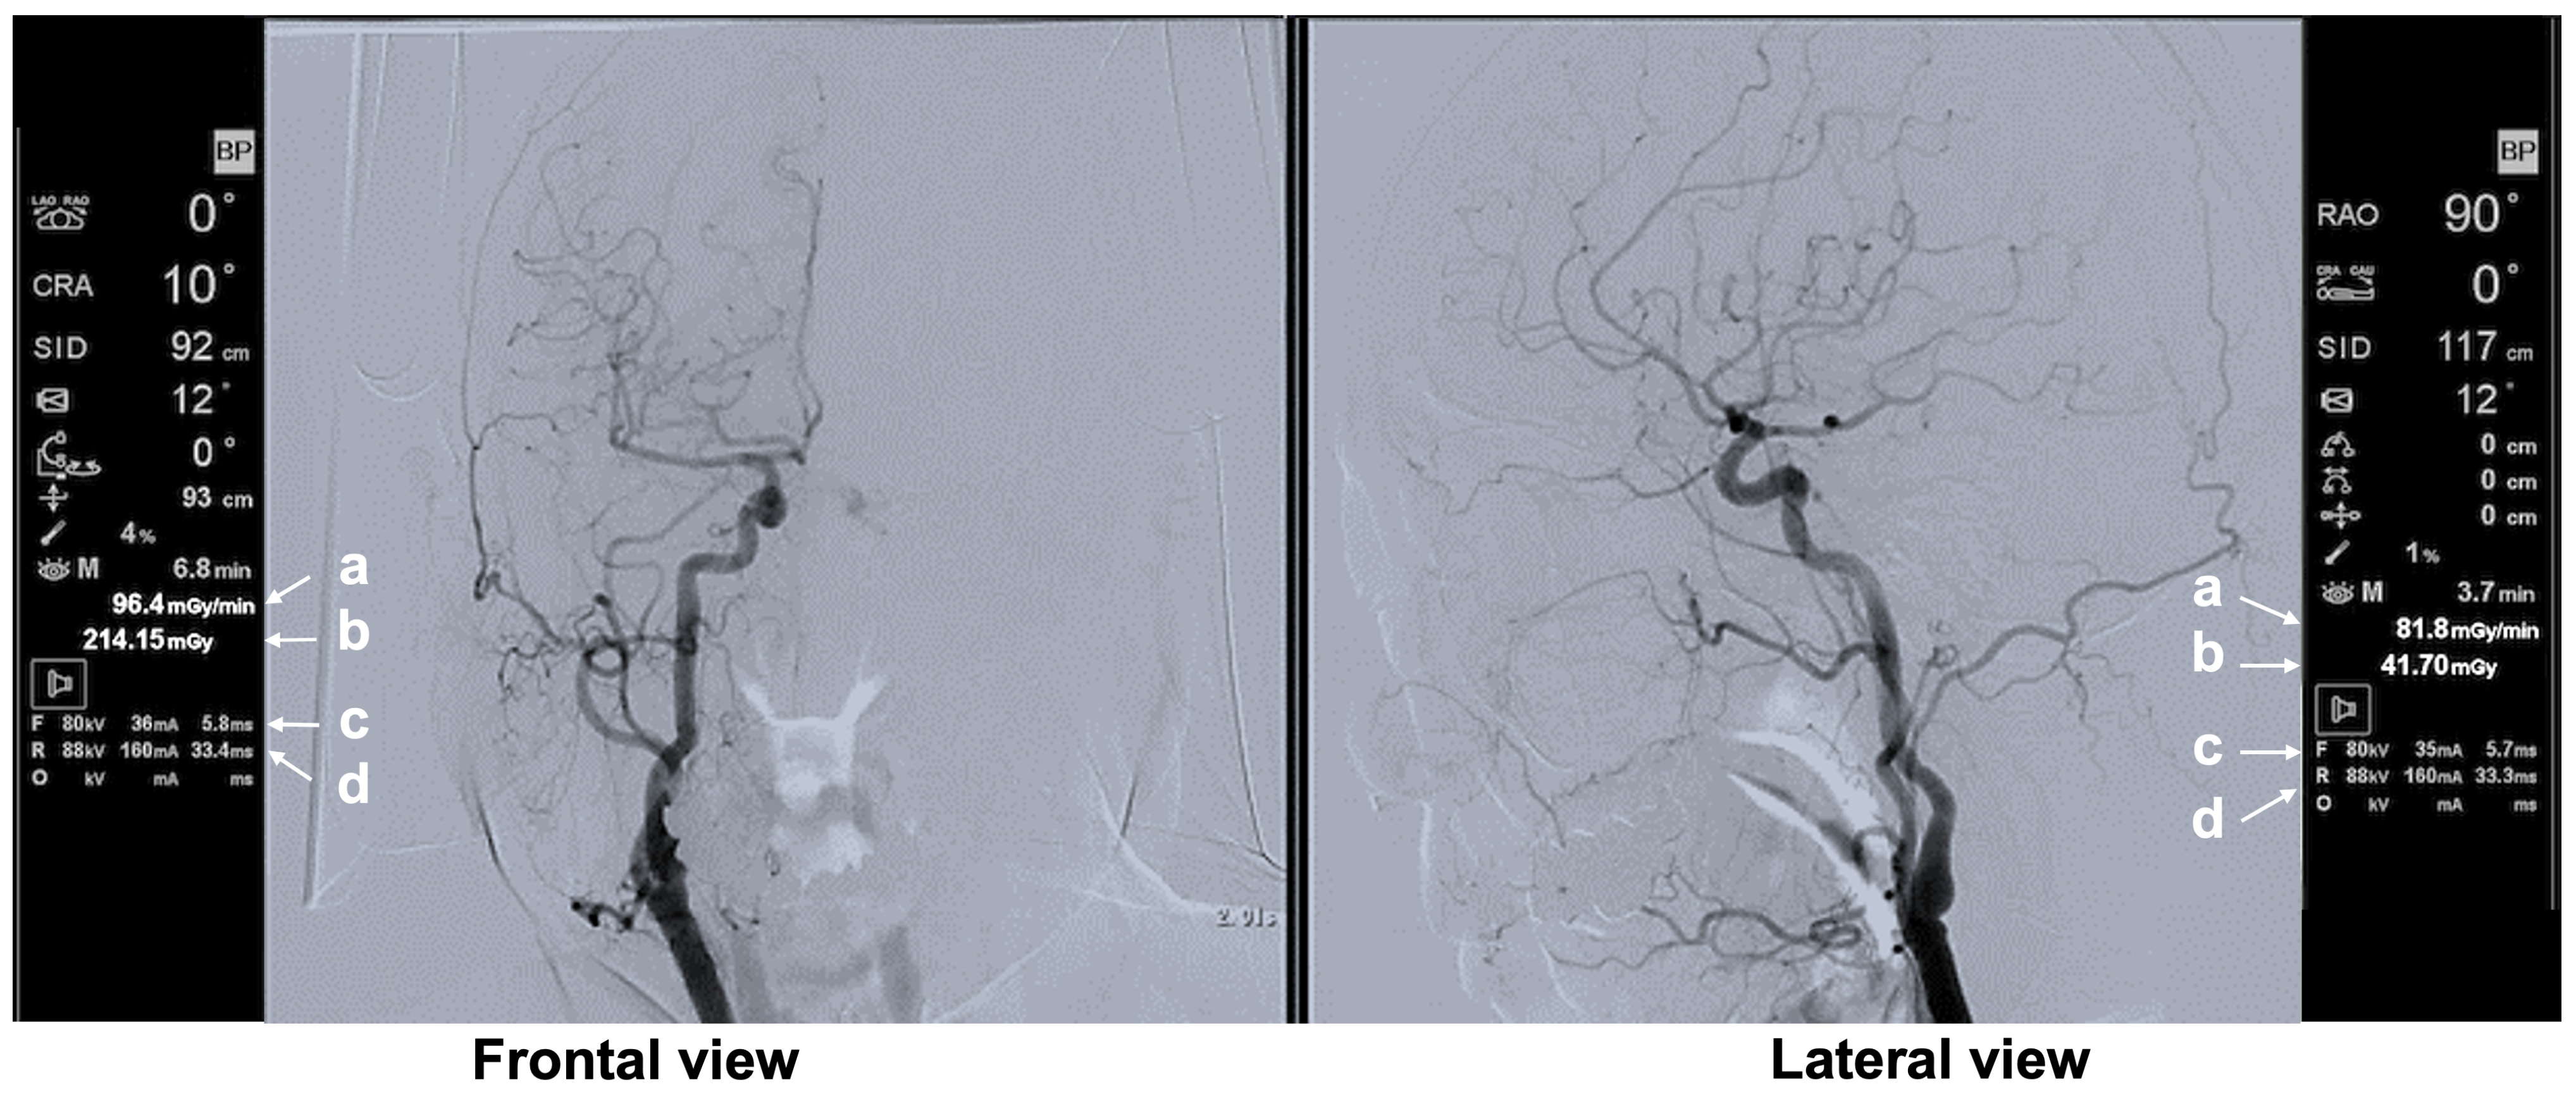

3.3.2. Typical Scene 2 (Case 5)

| Typical Scene No. | Case No. | DSA Site | X-Ray Projection | FPD Size (inch) | SID (cm) | Ka,r (mGy) | Table Height (cm) | Cervical Unprotected Dose Rate (mSv/h) | Chest Unprotected Dose Rate (mSv/h) | Cervical/Chest Unprotected Dose Rate Ratio |

|---|---|---|---|---|---|---|---|---|---|---|

| 1 | 5 | Rt FAG | Frontal—RAO 16°, Caudal 1° | 12 | 90 | 62.8 | 79 | 5.16 | 11.75 | 0.44 |

| 2 | 5 | Rt FAG | Frontal—LAO 20°, Cranial 0° | 12 | 90 | 70.4 | 87 | 11.29 | 35.27 | 0.32 |

| 3 | 3 | Lt C-CAG | Frontal—LAO 0°, Cranial 1° | 12 | 90 | 80.06 | 93 | 0.48 | 1.65 | 0.29 |

| Lateral—RAO 90°, Cranial 0° | 12 | 111 | 100.1 | |||||||